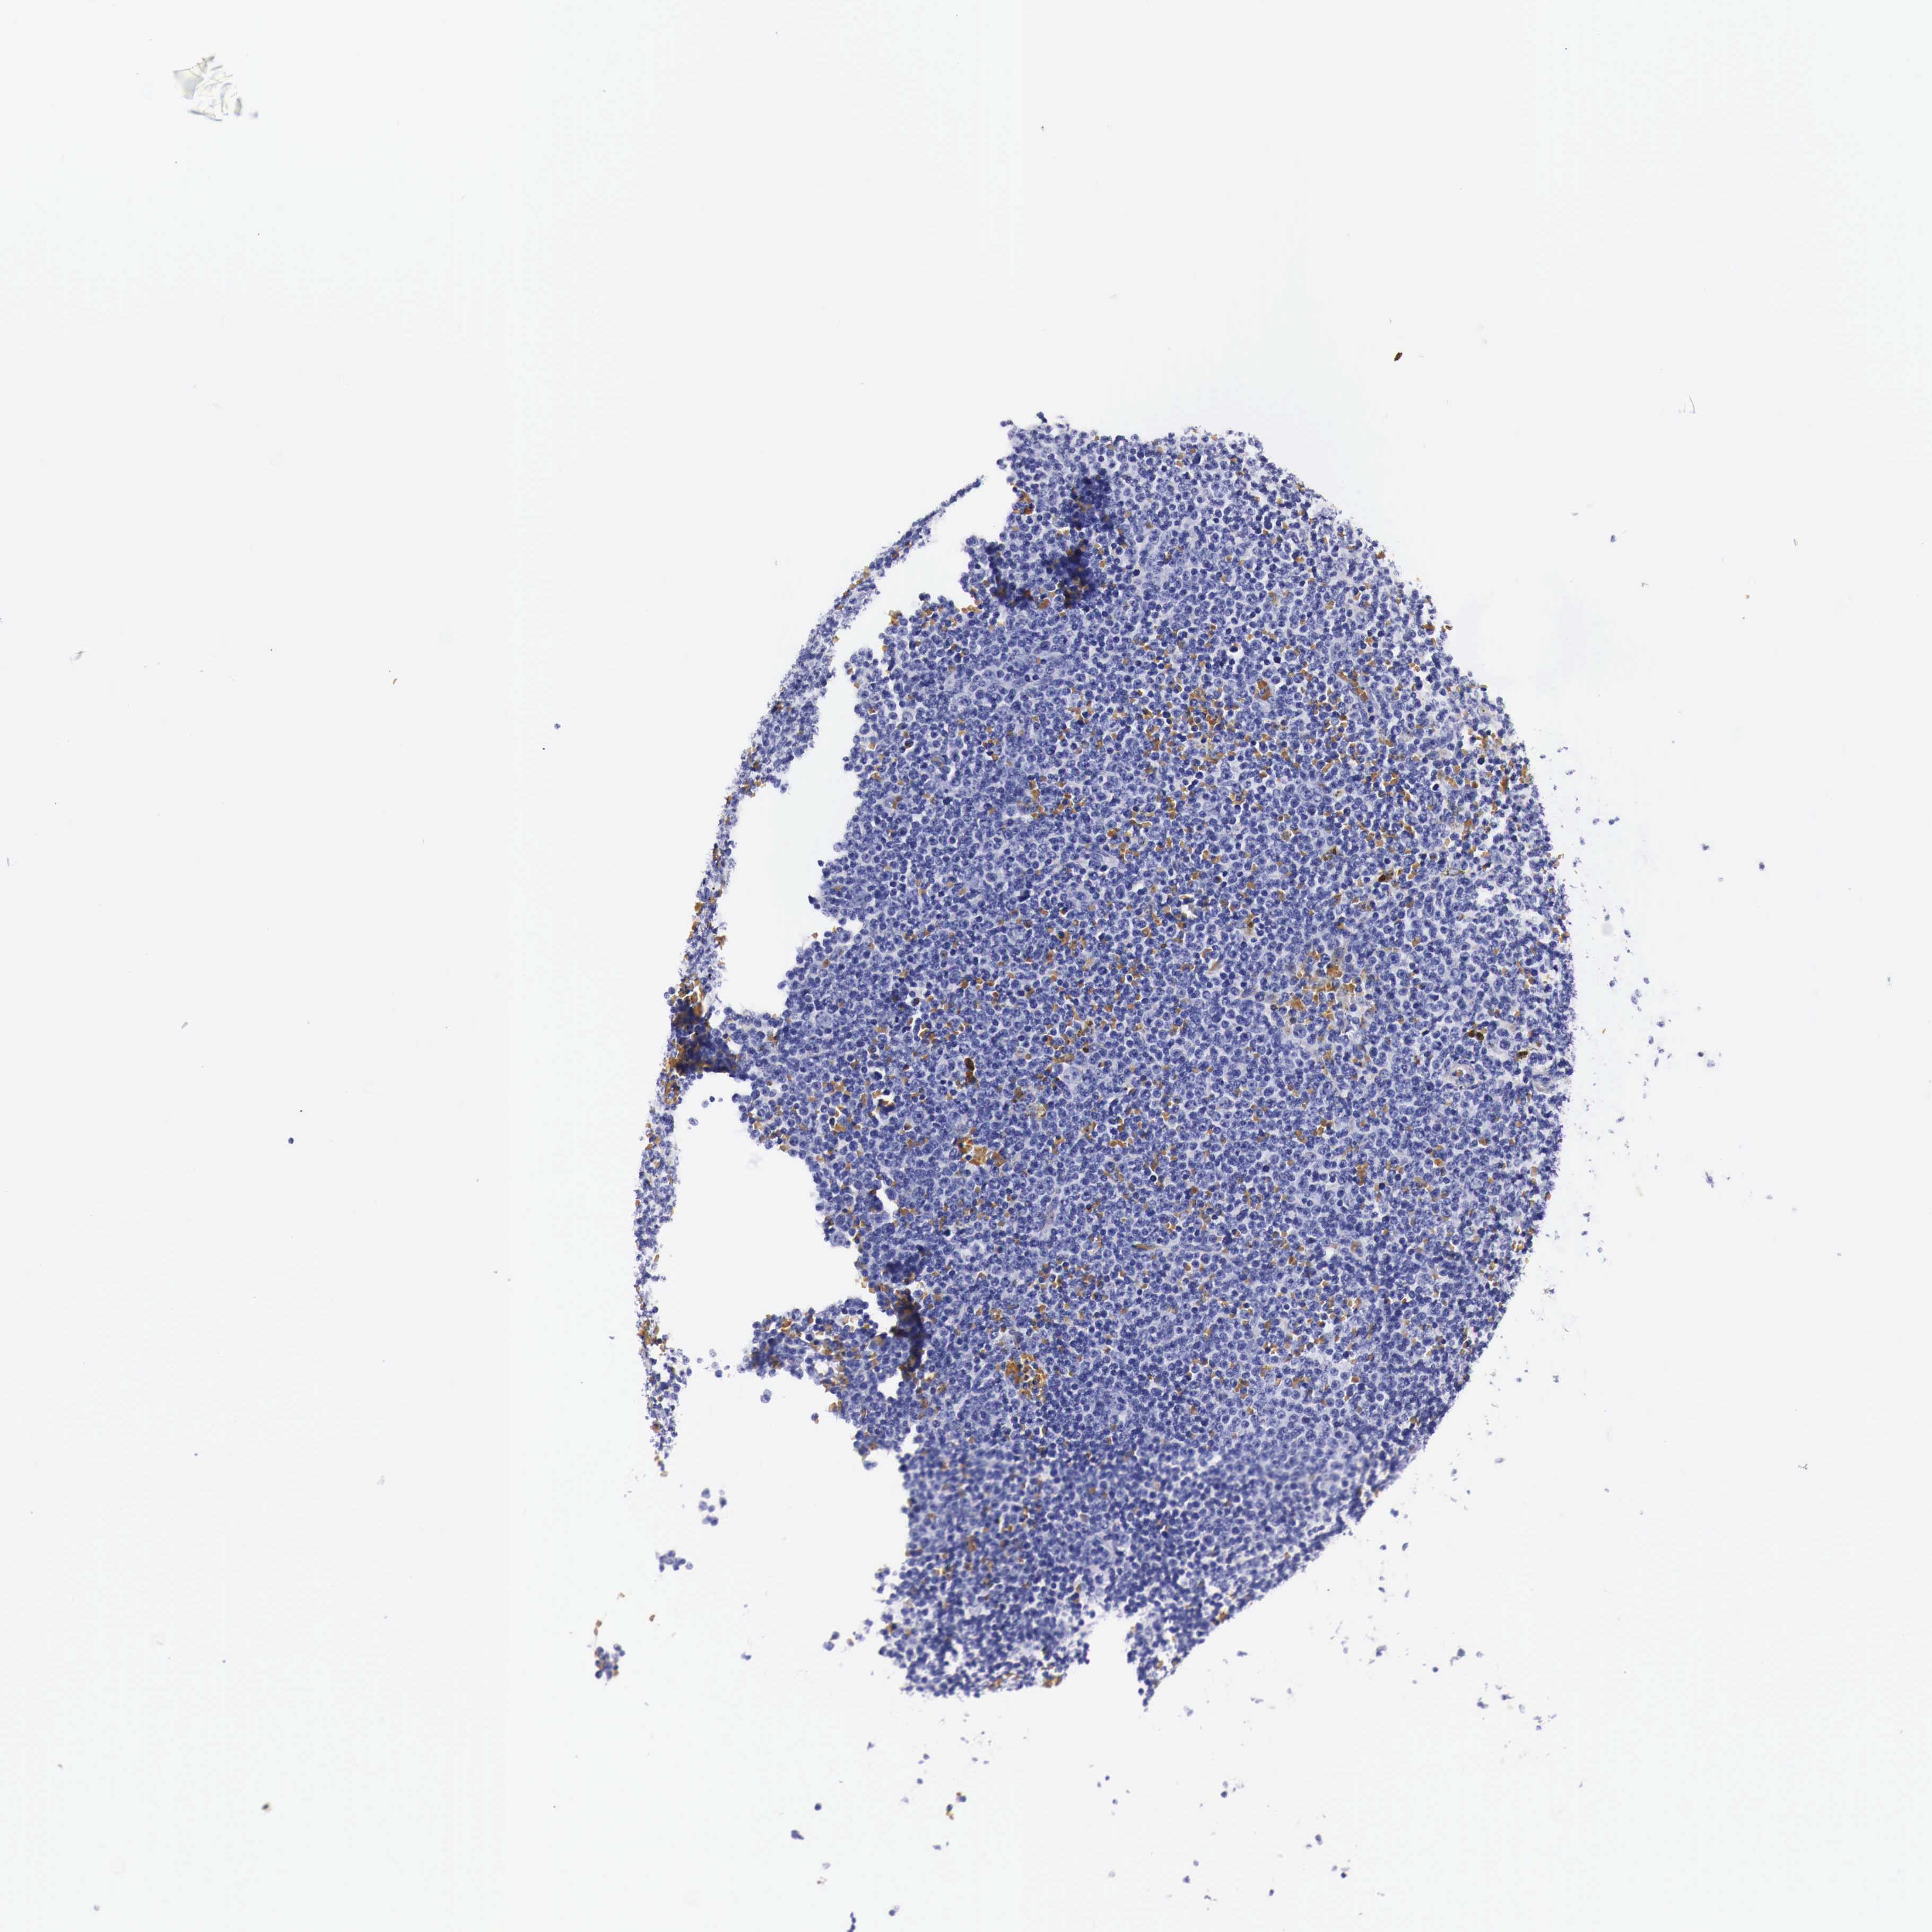

CANCER LYMPHOMA Show tissue menu

LYMPHOMA - Protein expressioni

A mouse-over function shows sample information and annotation data. Click on an image to view it in a full screen mode. Samples can be filtered based on level of antibody staining by selecting one or several of the following categories: high, medium, low and not detected. The assay and annotation is described here.

Each image is clickable and will lead to virtual microscopy that enables deeper exploration of all samples and also displays staining intensity scores, fraction scores and subcellular localization as well as patient and tissue information for each sample.

Malignant lymphoma, non-Hodgkin's type, High grade

Hodgkin's disease, NOS

Malignant lymphoma, non-Hodgkin's type, Low grade